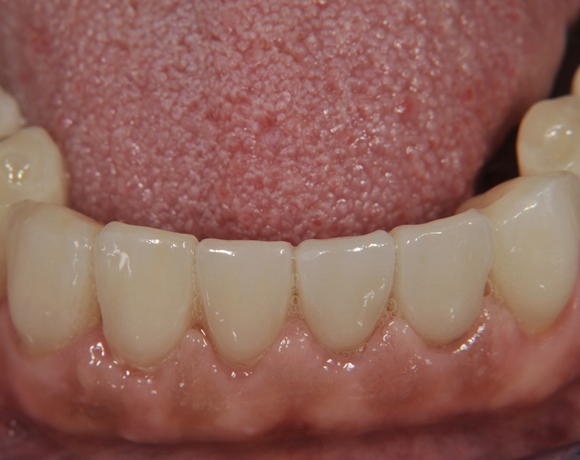

Der vorliegende Patientenfall zeigt eine komplette Neuversorgung der vorhandenen Metallkeramikkronen mit vollkeramischen Restaurationen. Zusätzlich wurde im Oberkiefer die Zahnreihe mit zwei Implantaten, für die fehlenden Molaren, ergänzt. Da keine ausreichende Knochenhöhe vorhanden war wurde ein interner Sinuslift geplant.